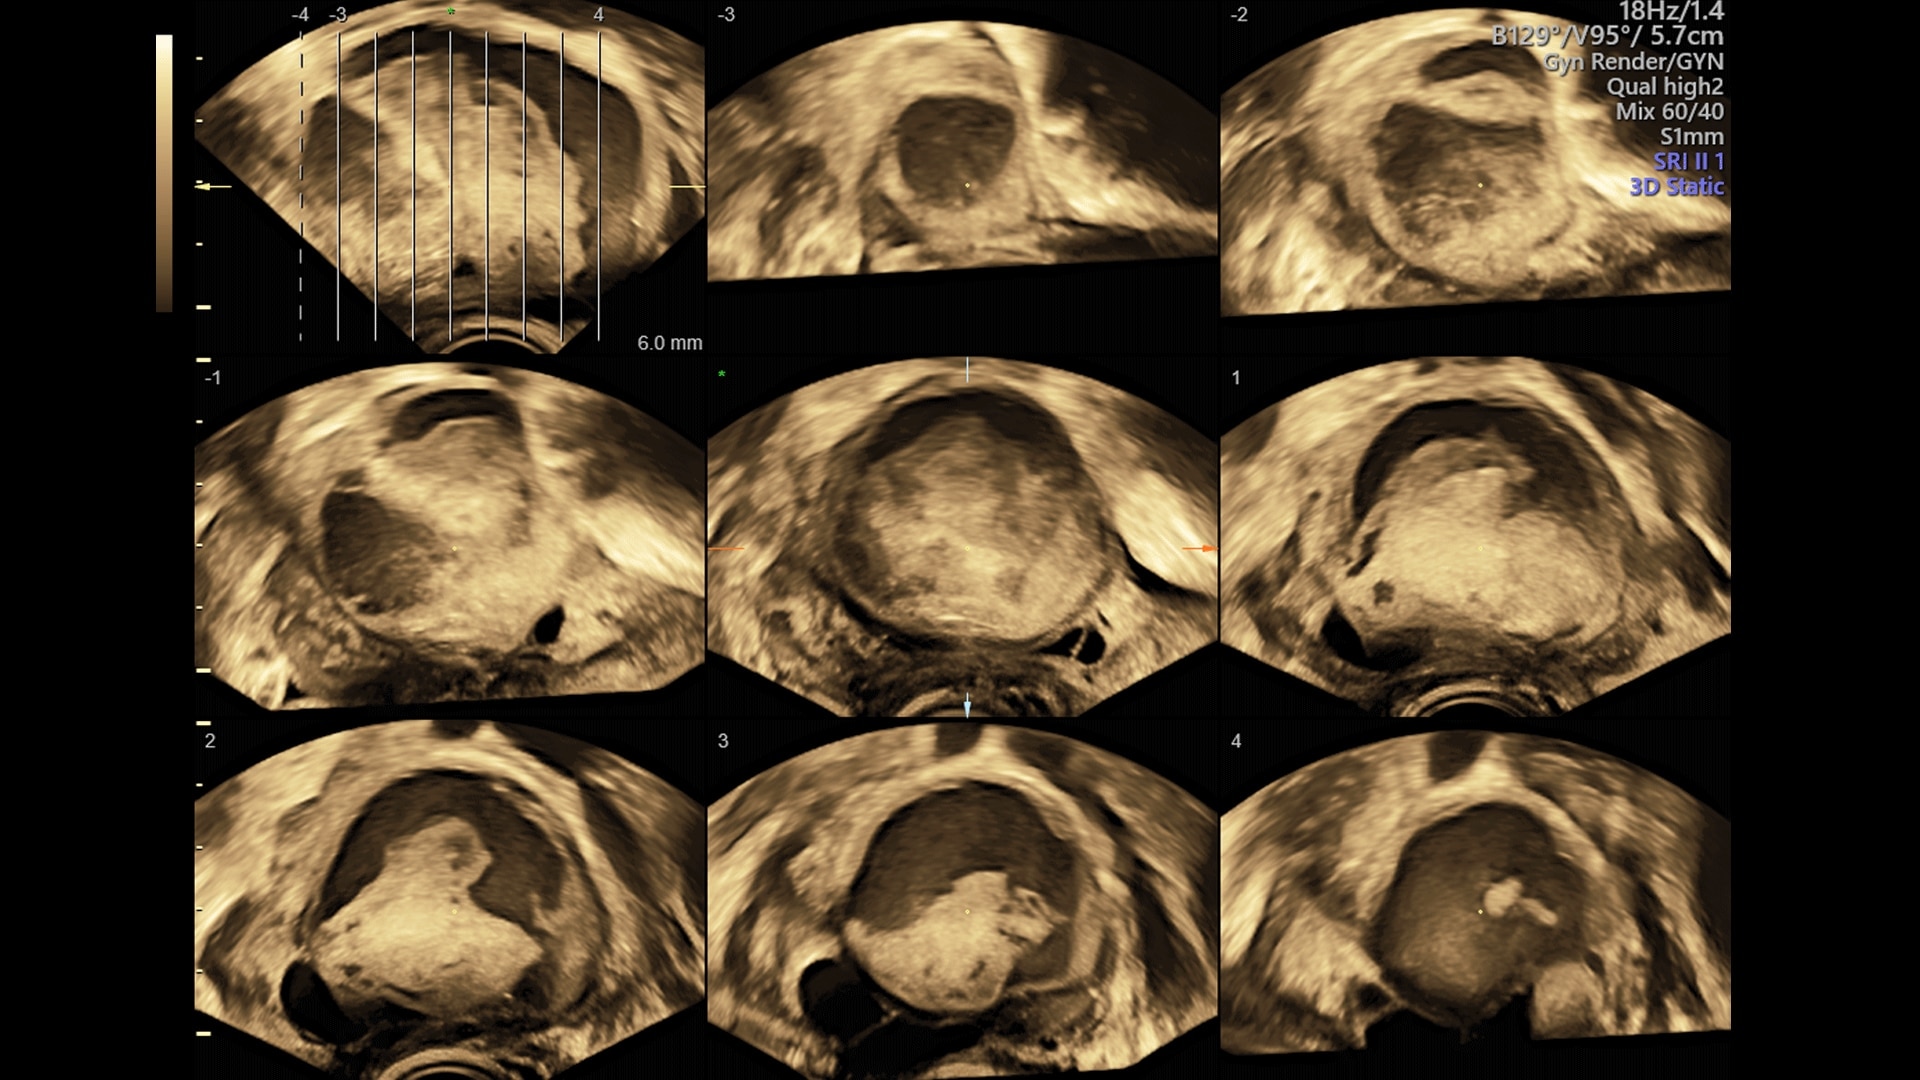

Uterine Trace

Incorporating 3D into your practice is easier than ever with Uterine Trace. From a standard view, simply trace the endometrium and the system automatically acquires a volume and then exacts the critical coronal view.

Volume Contrast Imaging (VCI)

Adjusts slice thickness on 3D or 4D images to help enhance contrast resolution using bone and tissue rendering techniques.